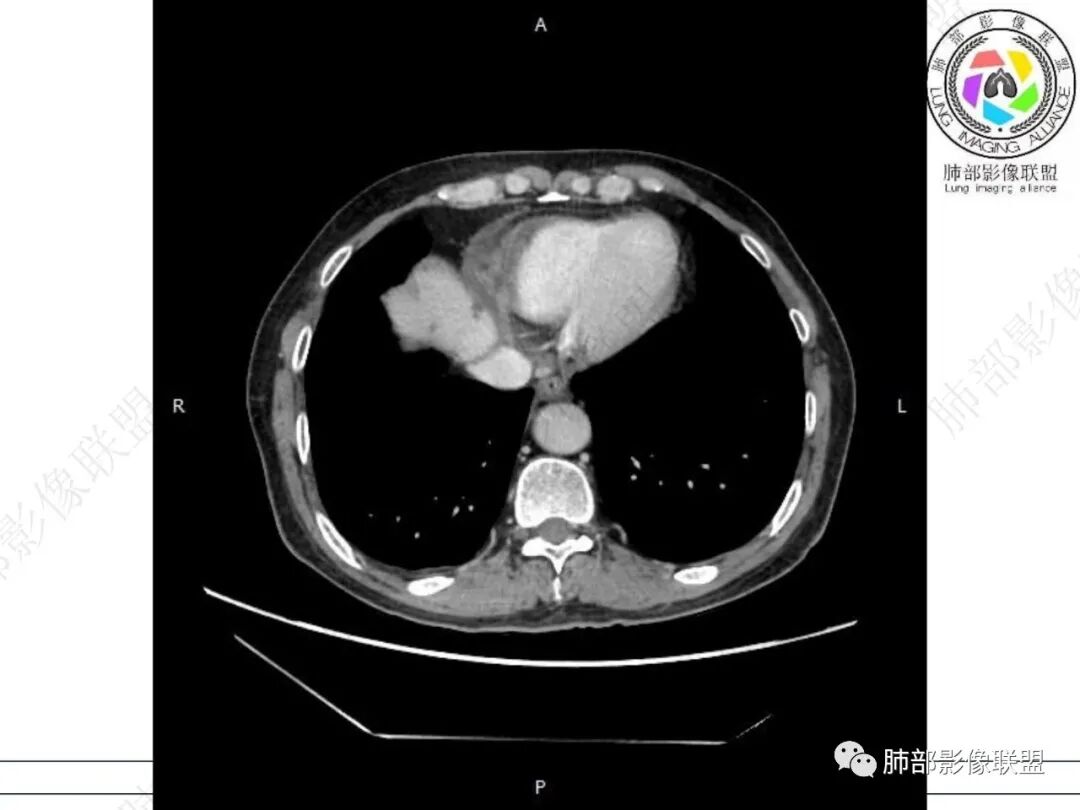

老年男性,慢性病程,右肺下叶斑片影、斑点影、实变影,支气管轻度扩张,病灶整体稍收缩;食道壁增厚、肿胀、模糊,气管隆突及右后纵隔旁见软组织块影,其内见气泡影,均匀强化,符合食道支气管瘘伴周围炎症,右下肺炎症

隆突下少量气体,隆突下团片状影,食管壁增厚,右肺下叶斑片状影明显强化,夹杂少量气体,纵隔瘘应该有,合并感染,食管肿瘤累及?临床没提食道症状,建议钡餐和内镜检查,没有看到体动脉供血,排除隔离症

右肺下叶沿肺叶肺段分布斑片、条片状影,以下叶背段为显,边缘模糊,内可见支气管走行,局部支气管管壁增厚,右侧胸腔少量积液。纵隔隆突下可见不均匀软组织密度影,与周围结构分界不清,内见气体密度影,与食管及相邻右肺支气管之间未显示通道。邻近食管下段壁明显不规则增厚,增强后食管管壁明显不均匀强化,可见线样强化的连续完整粘膜影。

右肺下叶片影,气道相关,符合感染性病变。纵隔隆突下软组织密度影,异常气体影,长病程,起病缓慢,提示存在气管或食管瘘。食管镜未见明显新生物形成,临床未提供进食或饮水呛咳临床表现,综合分析应该考虑支气管瘘的形成。